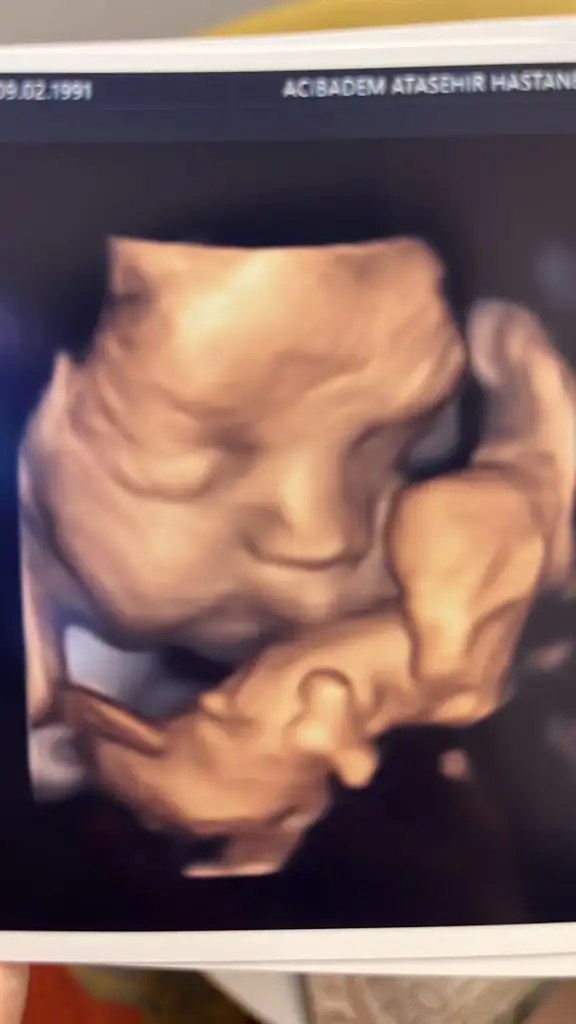

Maşallah ya balyanakSelam kizlar biz de kontrolden ciktik 29+3 1700gr olmus 31. haftayla uyumlu biraz onde dedi dr. Tombik diye dalga gectik diye kizdi hemen kapadi yuzunu. Burda da kordonu öpüyor “canim kordonum bana mama getirir”

Oyy masallahhhSelam kizlar biz de kontrolden ciktik 29+3 1700gr olmus 31. haftayla uyumlu biraz onde dedi dr. Tombik diye dalga gectik diye kizdi hemen kapadi yuzunu. Burda da kordonu öpüyor “canim kordonum bana mama getirir”

Oyyyy maşallahSelam kizlar biz de kontrolden ciktik 29+3 1700gr olmus 31. haftayla uyumlu biraz onde dedi dr. Tombik diye dalga gectik diye kizdi hemen kapadi yuzunu. Burda da kordonu öpüyor “canim kordonum bana mama getirir”

Oyyyy maşallaheee büyüklerimiz boşuma dememiş ekmek veren eli öpeceksin